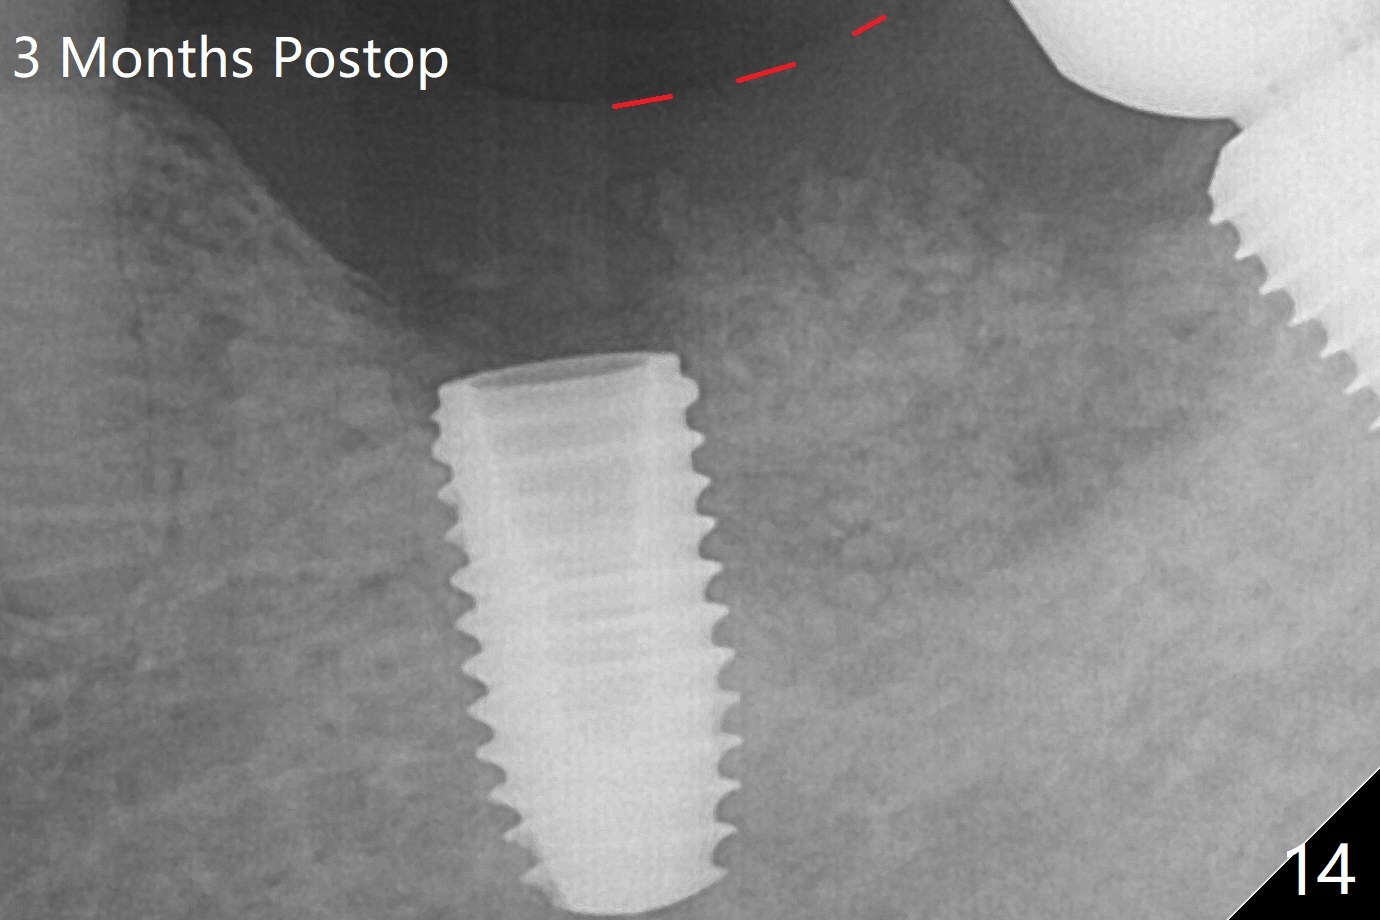

With 6 mm clearance, block anesthesia is administered. A 5x10 mm definitive implant is placed with ease (Fig.3). The buccal bony defect is repaired by allograft (*). The abutment has been dislodged for 2 week (Fig.14 (3 months postop). The bone graft, albeit decreased, is 2 mm subgingival (red dashed line).